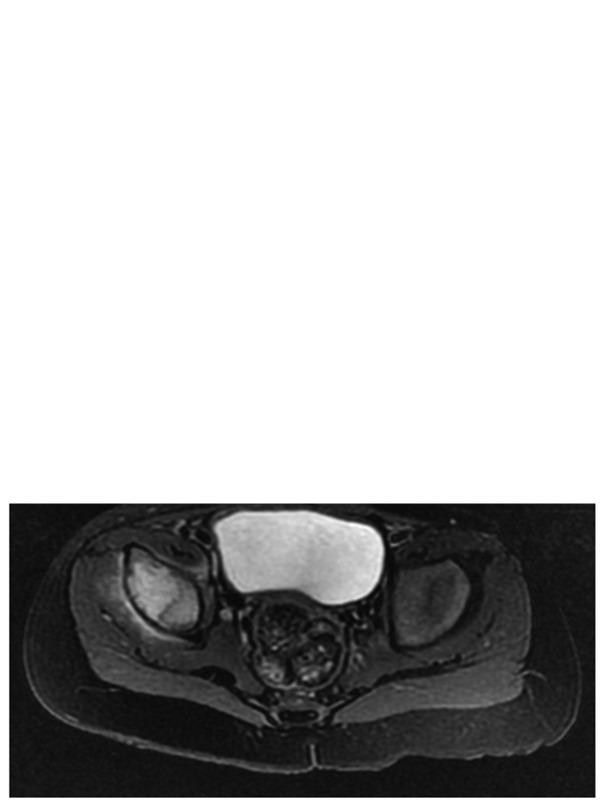

Rosai-Dorfman disease (RDD) is an extremely rare benign histiocytic disorder that usually affects young adults. Extranodal involvement of the RDD is common and may occur in >40% of patients, but bone involvement occurs in <10% of cases. Furthermore, primary bone RDD is extremely rare. The present study reports a case of primary bone RDD arising in the infantile ilium. Plain radiographs and computed tomography (CT) revealed an osteolytic lesion at the peri-acetabular region of the patient's right ilium. Fluorodeoxyglucose positron emission tomography indicated an abnormal accumulation only in the right iliac bone, without any other accumulation. An open biopsy was performed and the diagnosis of primary RDD of bone in the ilium was made. The bone lesion exhibited spontaneous regression on radiography, and the patient was able to walk without any limping or pain at 8 months after the biopsy. After 18 months of follow-up, the bone lesion had completely disappeared, and no joint deformity was observed on radiography or CT. The present report described the clinicopathological details of this rare case and reviewed the relevant literature.

罗萨伊-多夫曼病(RDD)是一种极为罕见的良性组织细胞疾病,通常影响年轻人。RDD的结外受累很常见,可能发生在超过40%的患者中,但骨受累发生在不到10%的病例中。此外,原发性骨RDD极为罕见。本研究报告了一例发生于婴儿期髂骨的原发性骨RDD病例。X线平片和计算机断层扫描(CT)显示患者右髂骨髋臼周围区域有溶骨性病变。氟脱氧葡萄糖正电子发射断层扫描显示仅右髂骨有异常聚集,无其他部位聚集。进行了切开活检,诊断为髂骨原发性骨RDD。骨病变在X线片上显示自发消退,活检后8个月患者能够正常行走,无跛行或疼痛。经过18个月的随访,骨病变完全消失,X线片或CT检查未观察到关节畸形。本报告描述了这一罕见病例的临床病理细节并复习了相关文献。